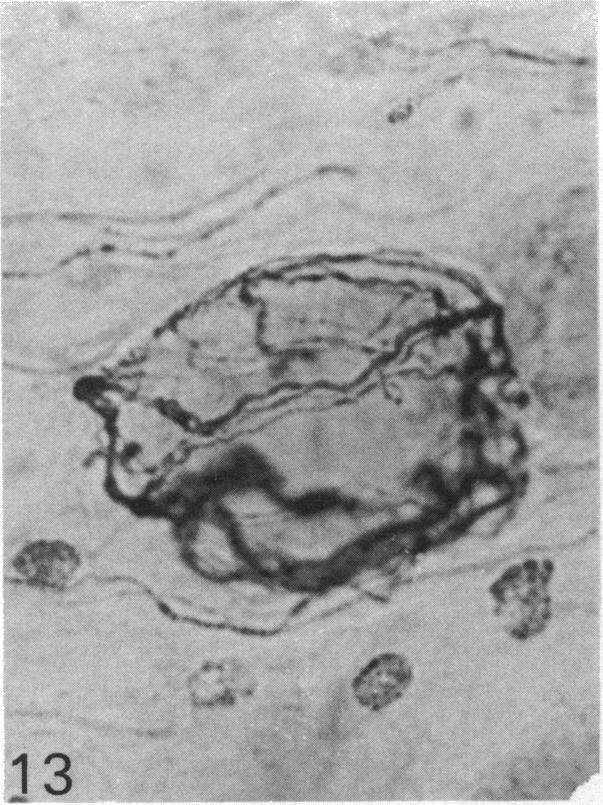

The quantitative cell count showed the presence of about 20,000 ganglion cells with associated satellite elements in the nodose ganglion in the monkey. Among these closely packed cells, at least one-third were substance P (SP) immunoreactive, ranging from faint or moderate to intense staining. Substance P immunoreactivity (SP-IR) was localised in the cell bodies and their long extending neurites. Ultrastructural study showed that SP-IR was not associated with any particular organelles or inclusions. A striking feature of the nodose ganglion was the occurrence of SP-positive pericellular arborisations associated with about 0.5% of the ganglion cells which were almost exclusively SP-negative. The pericellular arborisation displayed diverse morphological forms from a simple tortuous fibre to complex glomerular networks or plexuses encircling the soma of SP-negative ganglion cells. The varicose nerve fibres forming the pericellular arborisations appeared to terminate as 'boutons' contacting the soma of the ganglion cells. Electron microscopic study demonstrated the close spatial relation between the SP-IR profiles and the ganglion cell but there was no direct synaptic contact. In some instances, the SP-IR profiles containing agranular and dense-cored vesicles penetrated the cytoplasm of satellite cells, almost reaching the surface of the soma of the ganglion cell. The sources of origin of the nerve plexuses in the pericellular arborisation were either from the small and sparsely distributed jugular ganglion cells which were intensely SP-IR or from the intrinsic SP-IR nodose ganglion cells. The possibility that the efferent neurons in the dorsal motor nucleus of the vagus could also contribute to the pericellular arborisation was also considered. The function of the pericellular arborisations may be related to the modulation of the SP-deficient ganglion cells with which they associate through the release of SP and probably by way of the satellite cells.

定量细胞计数显示,猴子的结状神经节中存在约20,000个神经节细胞及相关的卫星细胞。在这些紧密排列的细胞中,至少三分之一对P物质(SP)呈免疫反应性,染色强度从微弱、中等至强烈不等。P物质免疫反应性(SP-IR)定位于细胞体及其长延伸的神经突。超微结构研究表明,SP-IR与任何特定的细胞器或内含物无关。结状神经节的一个显著特征是,约0.5%的神经节细胞周围出现SP阳性的树枝状分支,而这些神经节细胞几乎完全为SP阴性。细胞周围的树枝状分支呈现出多种形态,从简单的曲折纤维到复杂的肾小球样网络或围绕SP阴性神经节细胞胞体的丛状结构。形成细胞周围树枝状分支的曲张神经纤维似乎以“终扣”的形式终止于与神经节细胞胞体接触处。电子显微镜研究显示,SP-IR结构与神经节细胞之间存在紧密的空间关系,但没有直接的突触联系。在某些情况下,含有无颗粒和致密核心小泡的SP-IR结构穿透卫星细胞的细胞质,几乎到达神经节细胞胞体表面。细胞周围树枝状分支中的神经丛来源要么是来自强烈SP-IR的小而稀疏分布的颈静脉神经节细胞,要么是来自结状神经节内源性的SP-IR细胞。迷走神经背运动核中的传出神经元也可能参与细胞周围树枝状分支形成的可能性也被考虑在内。细胞周围树枝状分支的功能可能与其通过释放SP并可能通过卫星细胞对与之相关的SP缺乏神经节细胞的调节有关。